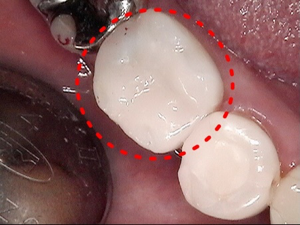

5.セット

口腔内へセットし噛み合わせの調整をして

治療完了となります。

先進的な接着技術を用いて、

削り出されたセラミック歯を口腔内へセットします。

最短でその日のうちに治療完了となります。